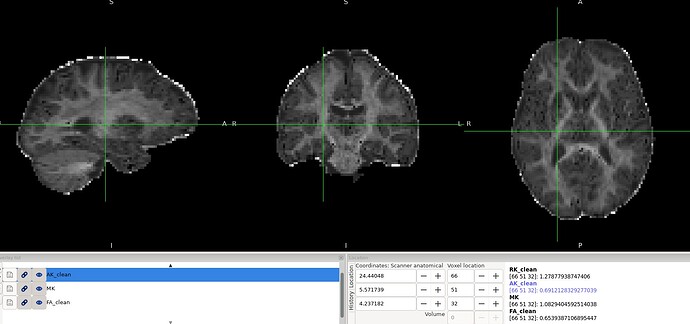

Overall, the results look reasonable; however, as shown in the image, there are a few black voxels, corresponding to values that are lower than expected, in the splenium and genu of the corpus callosum.